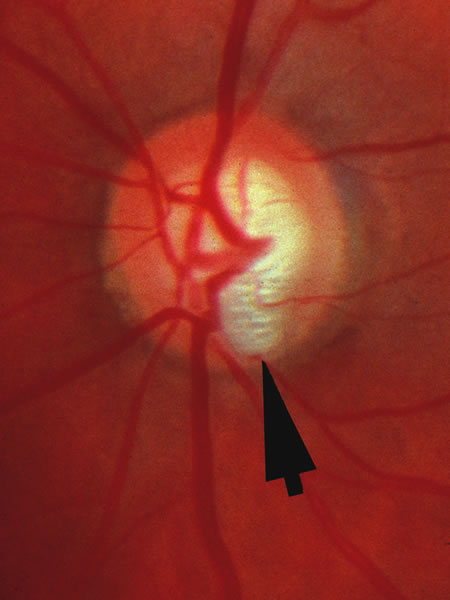

The approximately 1 to 1.5 million axons that form the optic nerve arise from the retinal ganglion cells and course toward the optic disc in a well-known pattern (Fig. 1). From the nasal retina the fibers take a straight course toward the disc. Axons originating temporal to the fovea arc around the macula to enter the upper and lower poles of the optic nerve head. The macula fibers pass directly to the temporal quadrant of the disc in the papillomacular bundle.

Fig. 1. Fundus photograph shows the normal pattern of the retinal nerve fiber layer. (Courtesy of P. Juhani Airaksinen, MD).